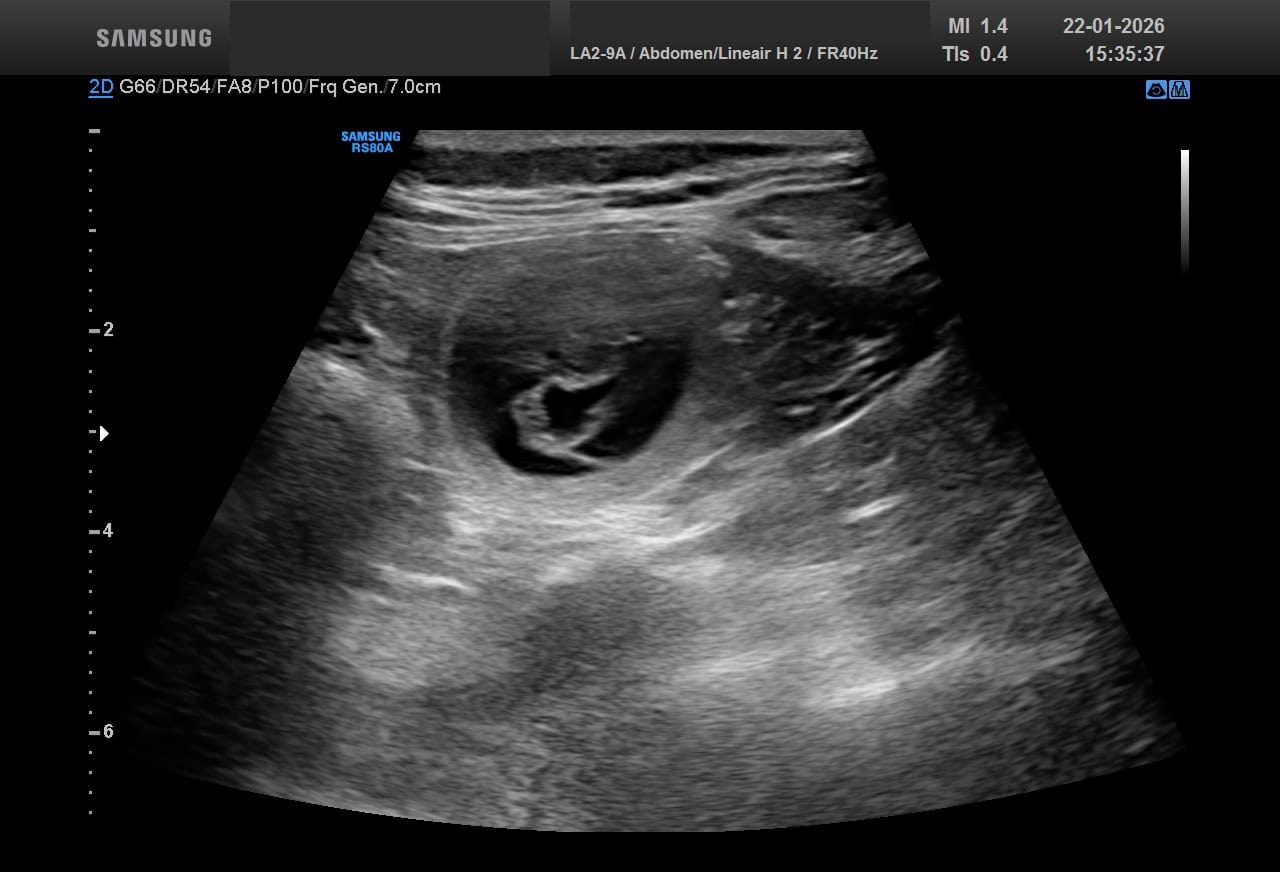

Gistermiddag was op dag 25 de echo van Nayeli. Dat ze drachtig zou zijn dat had ik wel verwacht gezien haar gedragingen maar ik had ook verwacht dat er wel een behoorlijk aantal pupjes in haar buikje zou zitten en dat is niet zo: Nayeli gaat een klein nestje krijgen. Ik ben doorgaans grote en hele grote nesten gewend dus dit is ook weer eens iets anders. Hieronder 2 afbeeldingen van de echo van gister: